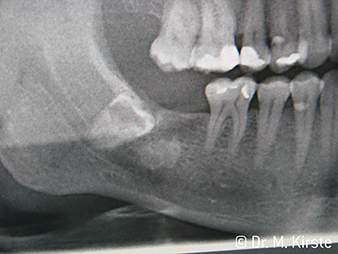

Cerrahi angldruvalar WS-91 ve WS-91 L G cerrahi piyasemen ve angldruvaların avantajlarını birarada sunan ilk ürün(Fig. 1). Gövde ve frez arasındaki açının genişletilmesi hem oklüzalden hem bukkalden iyi erişim sağlar(res. 4). Gömük dişler rahatlıla sökülebilir(res. 6 ve 7). Diş hekimi ayrıca eski cerrahi aletlerinde olduğundan daha iyi bir görüş açısına sahip.Frankfurt/Oder'den Dr. Mario Kirste şöyle diyor, “Eğer angldruva kafa açısını açabilirsem arka molar bölgede daha hızlı ve güvenli çalışabilirim. Bu angldruva , piyasemen ve angldruva kullanıcıların çalışma pozisyonlarına denk gelecek potansiyele sahip.” (res. 2-5)